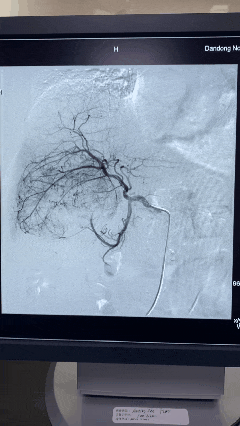

术中栓塞前DSA造影图像